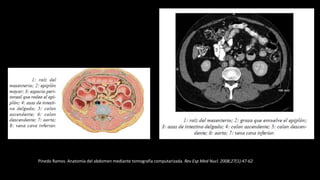

Pinedo Ramos. Anatomía del abdomen mediante tomografía computarizada. Rev Esp Med Nucl. 2008;27(1):47-62

1: aorta; 2: raíz del mesenterio; 3: tronco

celiaco; 4: hígado;5: estómago; 6:

páncreas; 7: colon; 8: saco menor; 9:

tercera porción de duodeno; 10: asas de

intestino delgado; 11: sigma; 12:receso

peritoneal (saco de Douglas); 13: recto; 14:

vejiga; 15: diafragma urogenital (cierra la

cavidad abdominal).